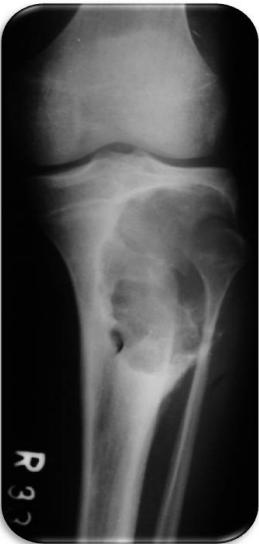

Giant Cell Tumor

Aneurysmal Bone Cyst

Epiphyseal-Metaphyseal Lesions

Benign aggressive lesions:

- Giant Cell Tumor (GCT)